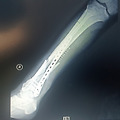

그래도 전에 두번 넘어진 경력으로 낙법을 숙지하여 잘 넘어졌지만 불법유턴차를 먼저 충돌하는 과정은 예상치못해 왼쪽 허벅지 뼈를 산산히 내주고 말았습니다.

다리에 철 박고, 뼈가 붙는 과정에 맥없이 누워있는 시간증에 허리 통증이 제일 심하데요. 많은 생각이 병실에 꽉 찹니다. 밖에 비가오는 모양입니다. 늘 건강하시고요...

여러분의 응원으로 아주 빠른 속도로 쾌차하고 있습니다. 감사합니다 꾸벅. 천만다행으로 다른데는 놀랄장도로 아무 외상이 없고 허벅지만 다쳤습니다. 좋아지고 있어 또 즐겁게 뵙겠습니다.

이렇게 보니 이해가 빠르군요. 저렇게 되어있구나... 몰랐습니다